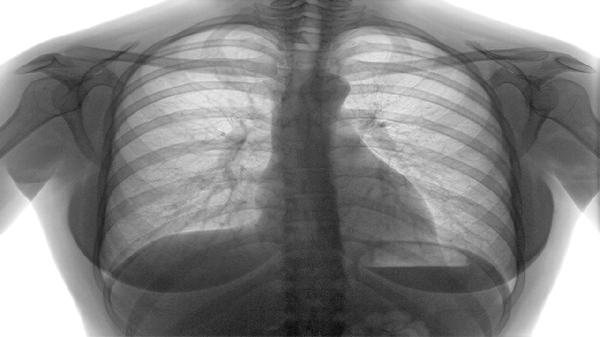

1、特殊成分帮助肺部功能

香蕉含有丰富的钾元素,这种物质对于维持肺部肌肉的正常收缩很关键。特别是对于慢阻肺患者,适当补充钾元素有助于减少呼吸肌肉疲劳。

2、缓解呼吸困难的营养支持

慢阻肺患者常伴随不同程度营养不良,香蕉提供的优质碳水化合物能快速转化为能量,为呼吸困难的身体提供及时补充。